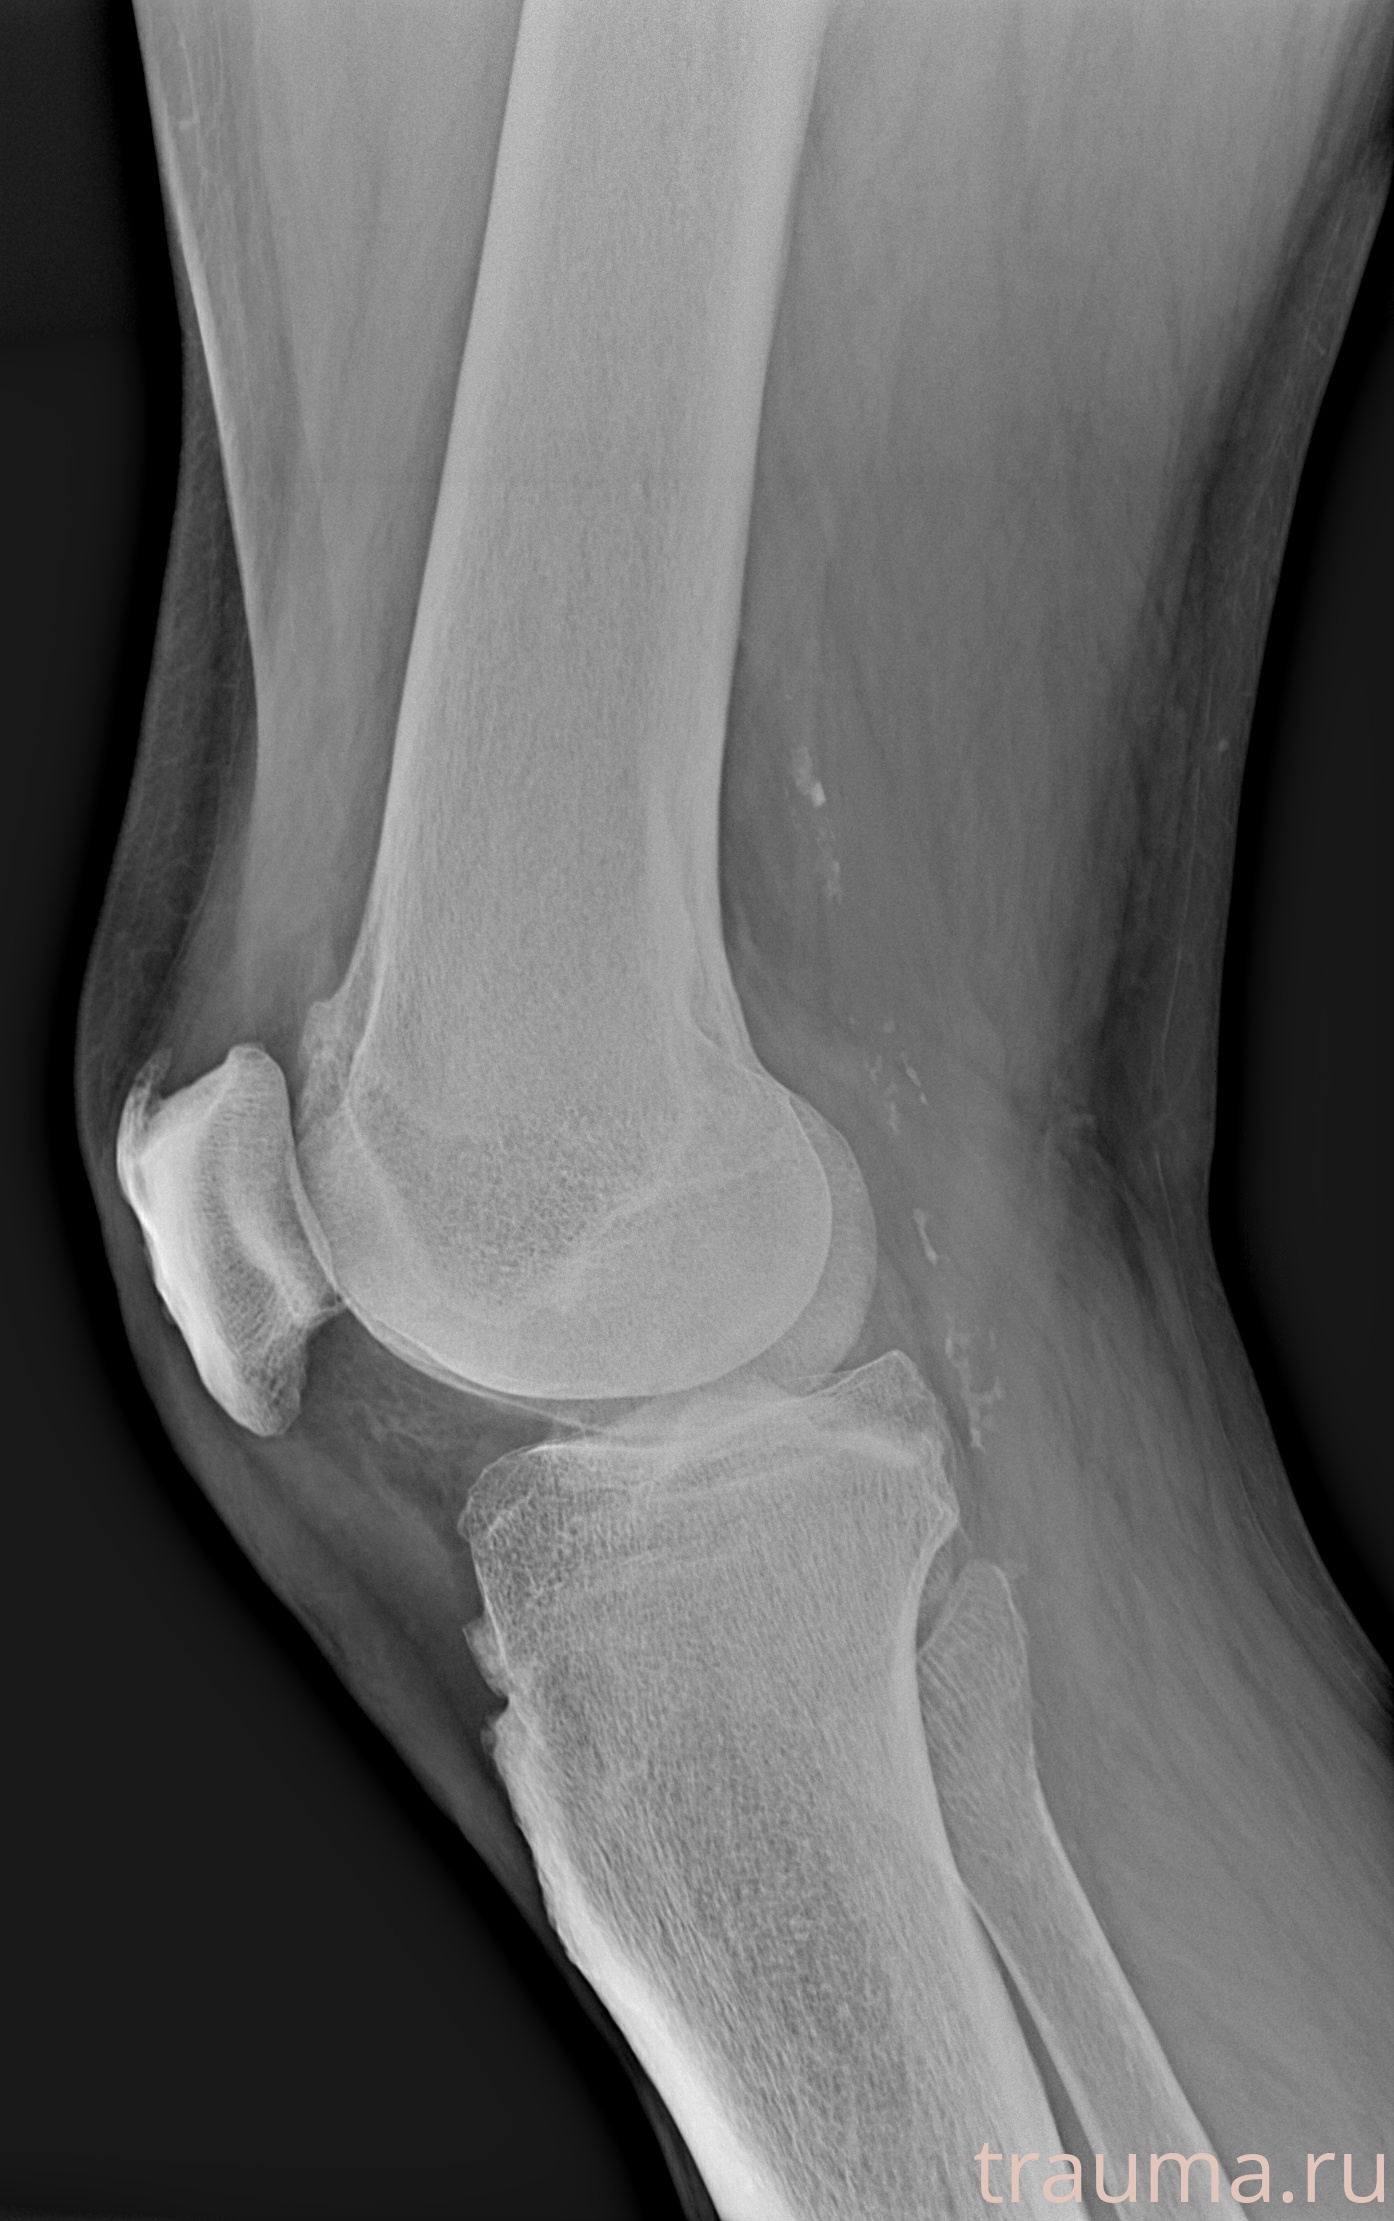

Рентгенограммы

Рентген на дому: по вашему адресу приезжает врач-рентгенолог, травматолог-ортопед с мобильным рентгеновским аппаратом, проводит диагностику травмы или заболевания, делает необходимые рентгенограммы, дает рекомендации по дальнейшему лечению. Получить качественные снимки в домашних условиях возможно благодаря уникальной методике, разработанной МосРентген Центром для института  Склифосовского